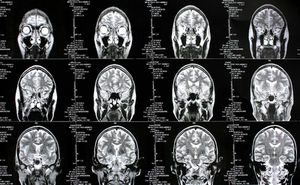

Gehirn: Scans zeigen Verhaltensstörung.